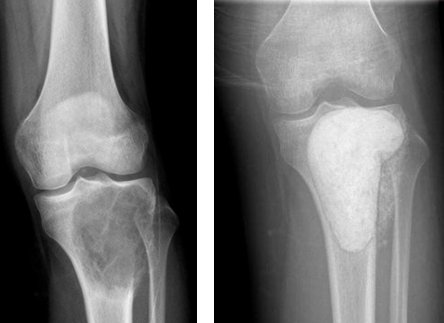

Giant cell bone tumor is also more common in young people. Although this type of tumor is mostly seen in the knee, it occurs in all parts of the body, especially in the joint areas (picture-10). It is usually in the form of blunt pain felt in the last few months. It can only be treated with surgery. The tumor is completely removed from the bone and the cavity is filled with bone cement or bone powders (pic-11). If the removal of the tumor is not done completely, recurrence is inevitable.